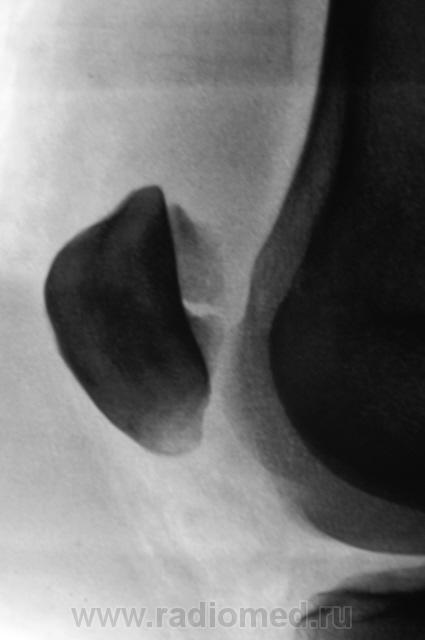

перелом надколенника( редко такой встречается) препателярная гемабурса, гемартроз, сильно пострадала суставная поверхность надколенника

Наверно все таки пателля бипартита. Представить, чтобы так красиво и ровно откололось - трудно... А мягкотканный компонент знатный...

Сам думал о "бипарцита", кстати, недавно был случай с "трипарцита". Но в данном случае был в растерянности, клиника "зашкаливает", конечно, возможно из-за мягкотканного компонента.

Кстати, на обычной рентгенограмме, произведенной в ургентных условиях "мягкотканный компонент" едва угадывается. Сильно "Сиар" спасает.

В минус травме говорит такая "красивенькая форма" отломка? НО при бипарите про мягкотканный компонент я данных ненашел..